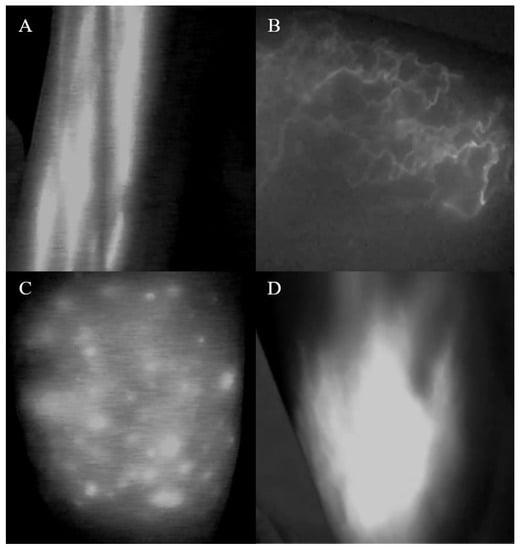

2.2. ICG Lymphography

3.3. Analysis of ICG Lymphography